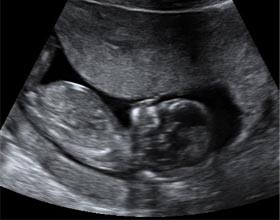

Se diferencian perfectamente la cabeza, los brazos, las piernas y el torso en la ecografía de la semana 13. Se aprecian las órbitas de los ojos y la boca abriéndose y cerrándose. Puede visualizarse al bebé chupándose el dedo. Es normal verle dando patadas y moviendo los brazos.

Aún se puede medir el pliegue nucal de tu bebé

En esta semana de gestación todavía se puede realizar la medición de la translucencia nucal como parte del test de cribado combinado. Algunos ginecólogos realizan solo la medición del pliegue o translucencia nucal como cribado de aneuploidías, en lugar del cribado combinado que utiliza datos ecográficos y analítico.